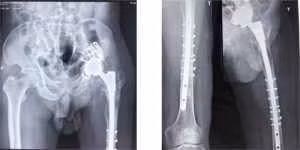

TS Nguyễn Quốc Dũng, Phó trưởng Khoa Phẫu thuật Khớp, Bệnh viện T.Ư Quân đội 108 cho biết, đây là một ca bệnh khó và phức tạp. Tại chỗ sẹo mổ liền tốt, mềm mại, chiều dài tương đối chân trái ngắn hơn bên phải 3cm nhưng kết quả chụp phim cho thấy, khớp háng nhân tạo trái toàn phần, có xi măng, có hình ảnh tiêu, thưa xương và đường thấu quang quanh cả ổ cối và xương đùi, chuôi khớp lún sâu, xét nghiệm hs-CRP và máu lắng trong giới hạn bình thường.

Điều đáng lo ngại là khớp bị lỏng, hỏng nhưng xi măng ngoài bám vào khớp còn bám chắc vào nền xương thưa yếu xuống tận gần gối. Tuy nhiên, đứng trước tình trạng BN vẫn còn khỏe, thể trạng tốt, các bác sĩ đã quyết định đưa ra phương án điều trị: Thay lại khớp háng trái toàn phần, không xi măng.

Hình ảnh khớp hỏng và tiêu xương trước khi thay.